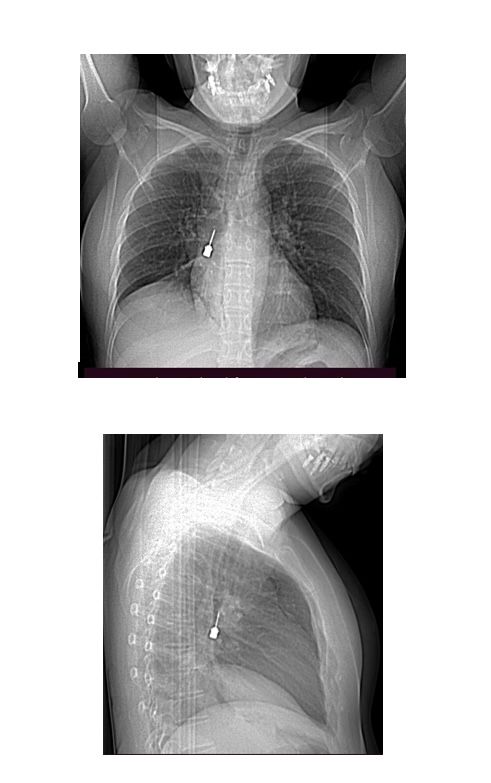

La paziente è giunta al Pronto Soccorso del G.O.M. esibendo un esame di diagnostica per immagini (Tomografia Computerizzata) eseguito a causa di una tosse persistente e di un forte dolore a livello toracico. La TC mostrava la presenza di un corpo estraneo metallico pericolosamente incastrato nel bronco lobare inferiore del polmone destro e un concomitante pneumomediastino, ossia la presenza di aria nello spazio compreso fra i due polmoni.